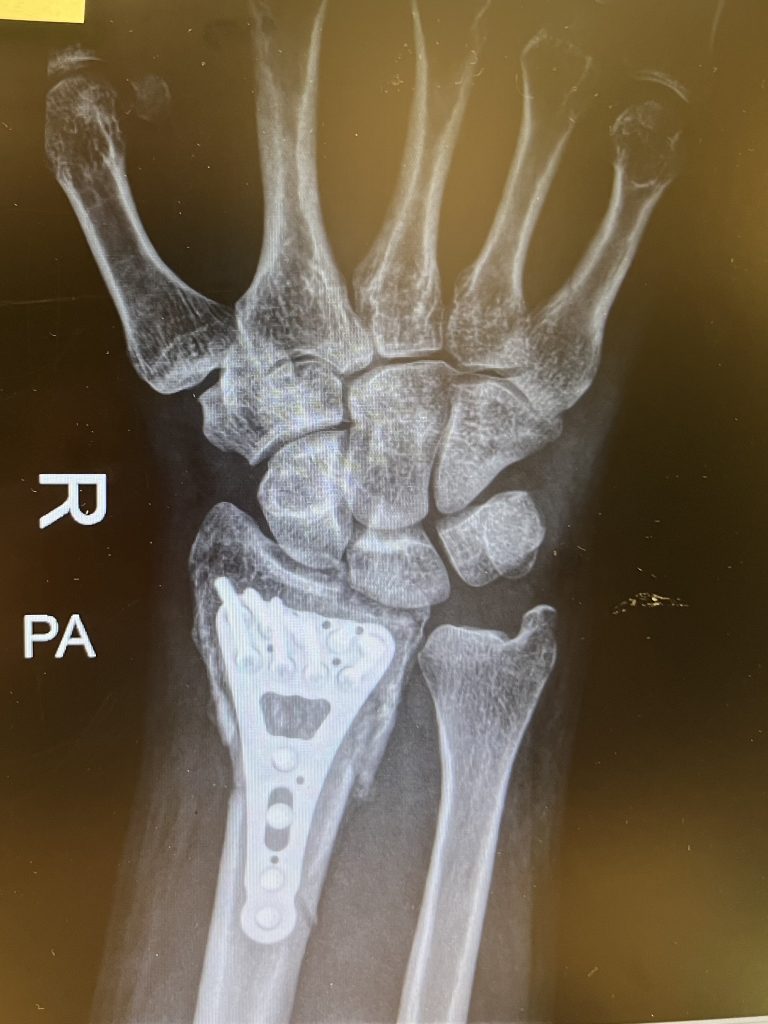

Shattered my radius, ended up in surgery — now I’m part human, part titanium. Basically a budget Wolverine. After 7 weeks of Netflix, naps, and pretending to do physiotherapy, I’m officially back at work. Fingers crossed the only thing I break from now on is my personal best at avoiding accidents!